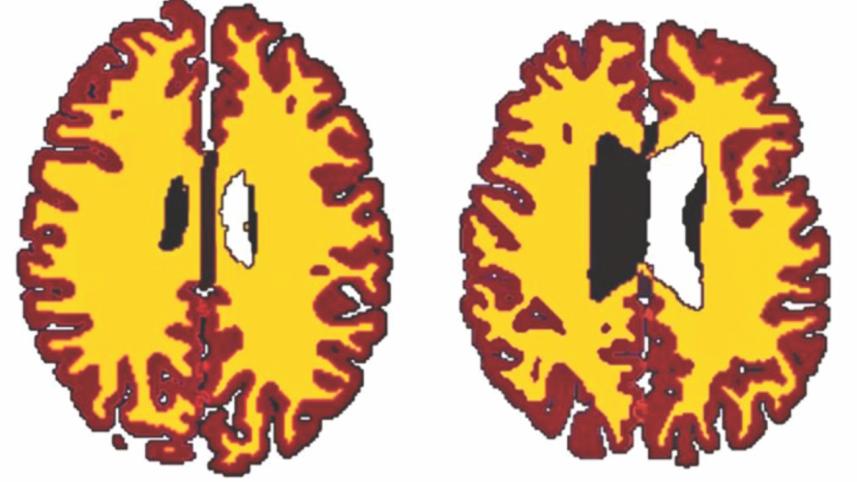

The brains of overweight people look "10 years older" than those of leaner peers, a study has found. Brains naturally lose white matter - the part of the brain that transmits information - as people age.

The team, from the Cambridge Centre for Ageing and Neuroscience, looked at the brains of 473 people aged between 20 and 87, dividing them into lean and overweight categories. Their findings, published in the journal Neurobiology of Aging, found significant differences in the volume of white matter in the brains of overweight people compared with leaner individuals. Those in the overweight group had much less white matter than their thinner counterparts.